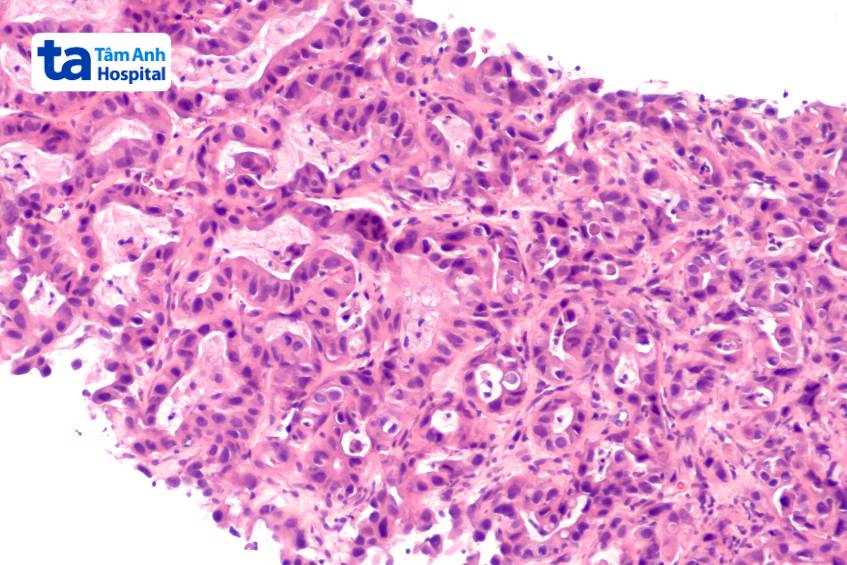

Sinh thiết gan qua da sử dụng hướng dẫn siêu âm là phương pháp chẩn đoán chính xác trong đánh giá mô bệnh học. Đối với chẩn đoán gan nhiễm mỡ do rượu, phương pháp này còn được coi là tiêu chuẩn vàng.

Mặc dù sinh thiết gan hiện đang là tiêu chuẩn vàng trong chẩn đoán gan nhiễm mỡ không do rượu nhưng vẫn tồn tại tỷ lệ rất nhỏ biến chứng. Cụ thể, tỷ lệ đau được báo cáo là 20%, tăng lên 84% nếu tính cả cảm giác khó chịu nhẹ. Tỷ lệ biến chứng nghiêm trọng và tử vong được báo cáo lần lượt là 0,3% – 0,57% và 0,01%. Để giảm biến chứng, bác sĩ thực hiện sinh thiết đòi hỏi phải có nhiều kinh nghiệm, đồng thời kết hợp sử dụng kim sinh thiết loại hút.